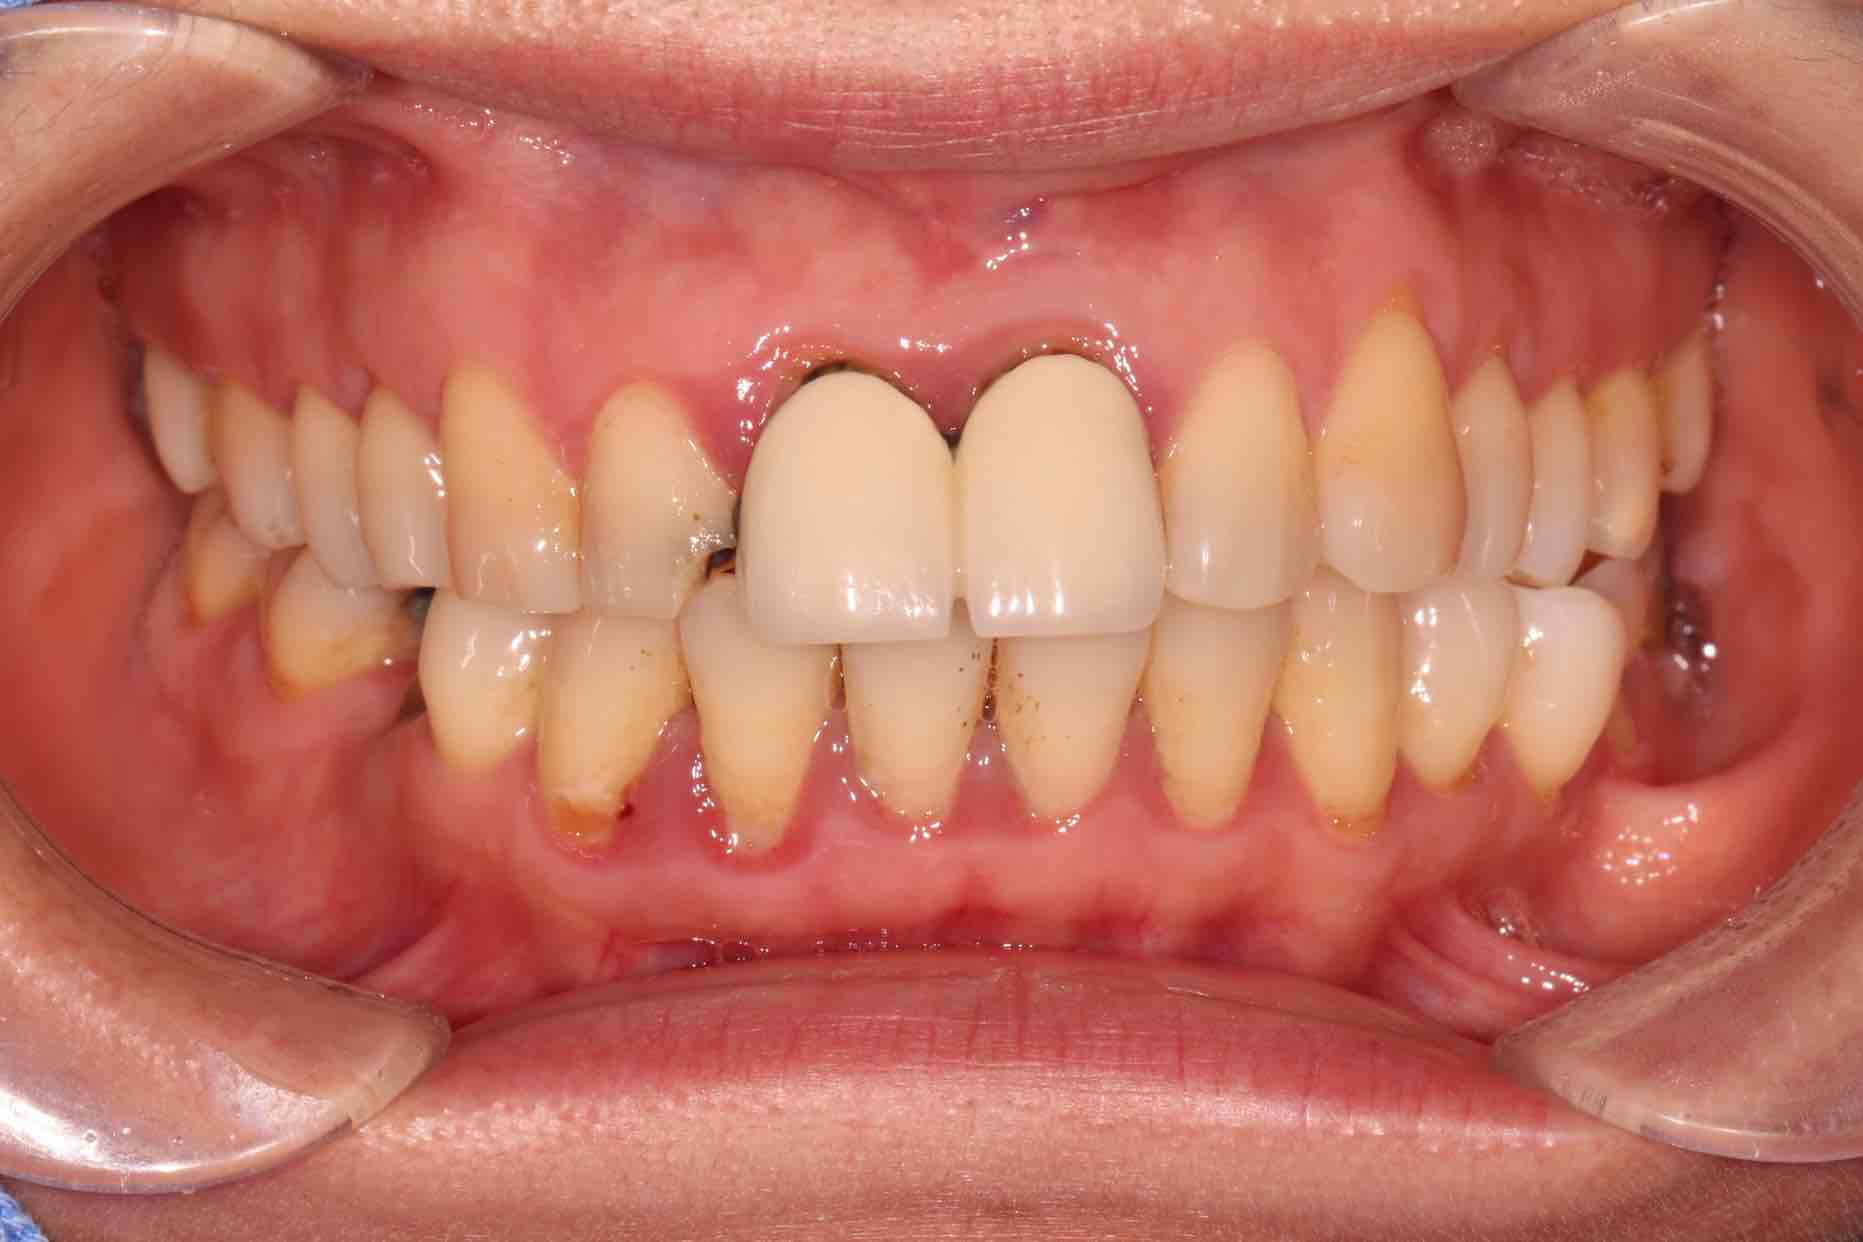

患者中年女性,11、21外院制作烤瓷冠,冠边缘不密合,牙龈退缩发黑,龈缘红肿,颜色不美观且X线检查21根管治疗不完善,由于牙冠不密合,11严重龋坏已有牙髓炎症状,我们对11进行了根管治疗,21进行了根管再治疗,最后CEREC扫描修复。